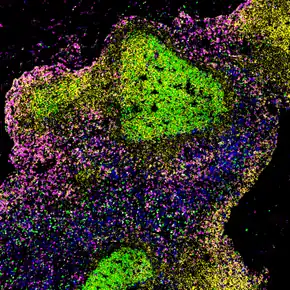

Biopsied lymph node with untreated HIV (shows large germinal centers containing abnormal proliferating B cells)